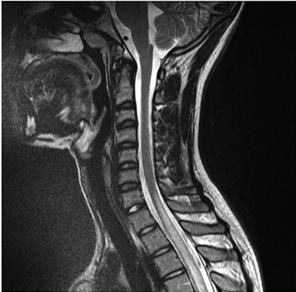

Paciente de 29 anos, sexo feminino, chega ao pronto atendimento apresentando fraqueza em membros inferiores, com três dias de evolução, que se associou à sensação de urgência urinária e constipação. Iniciou o quadro com alteração de sensibilidade nos membros inferiores e, no momento da admissão, não conseguia mais deambular. Na história pregressa, a paciente apresentava um quadro de artralgia e febre. No exame neurológico, entre outros achados, apresenta nível sensitivo em T2. Nos exames laboratoriais, observou-se pancitopenia, anti-DNA e anti-Sm positivos. A ressonância magnética da coluna cervical apresentou a seguinte imagem:

Em relação ao caso apresentado, é correto afirmar: